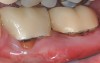

The consensus report from the AAP's work-shop group on intrabony defects presents evidence that periodontal regeneration in intrabony defects is possible on previously diseased root surfaces, demonstrated by gains in clinical attachments, reductions in periodontal pocket depths, gains in radiographic bone heights, and overall improvements in periodontal health.9 These clinical findings are consistent with available histologic evidence, and the clinical improvements can be maintained over long periods of time (ie, > 10 years).9 Although bone replacement grafts have been a commonly investigated modality, guided tissue regeneration, biologics, and combination therapies have also been shown to be effective. Early management offers the greatest potential for successful periodontal regeneration.9 Figure 9 through Figure 11 depict the treatment of a tooth with probing depths of equal to or greater than 15 mm using mineralized FDBA.

(12.) Pretreatment photograph of two previously restored teeth exhibiting gingival recession and probing depths equal to or greater than 15 mm.

Figure 12